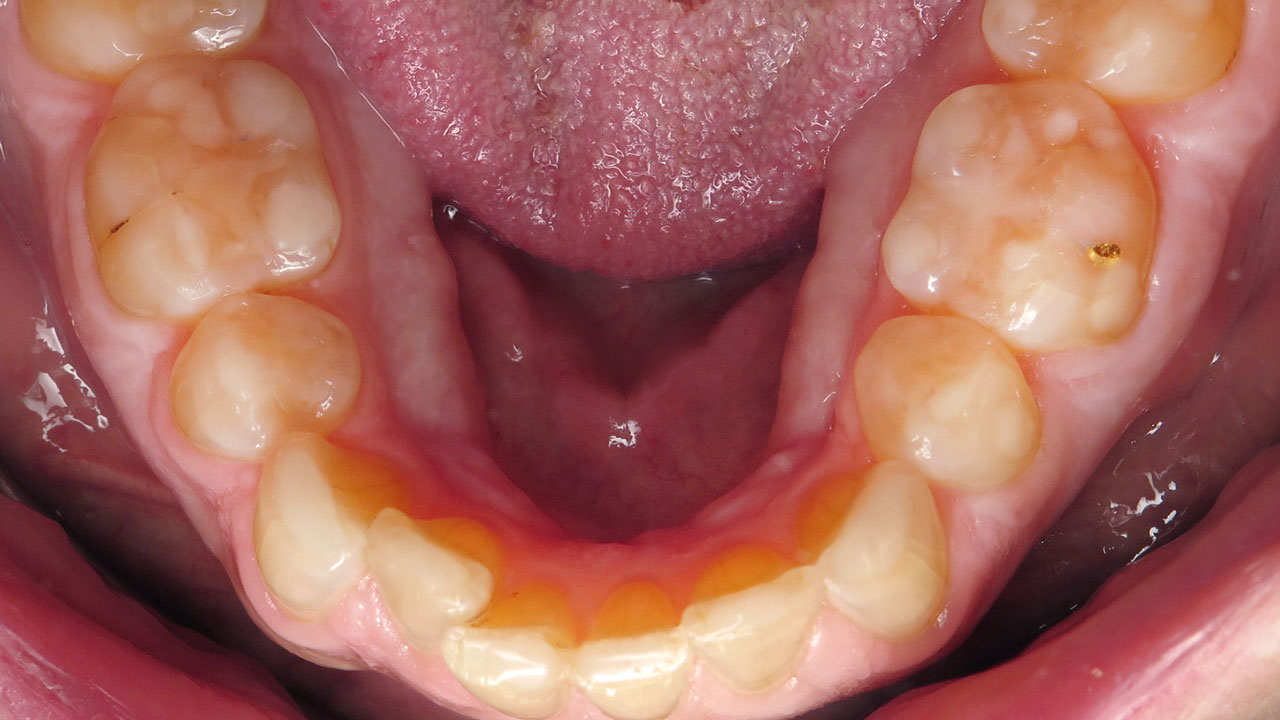

Removal of early decay and conservative bonding to restore the worn edges of the upper and lower front teeth.

Conservative composite bonding on six upper and six lower front teeth.

The worn edges were restored to a smoother, more protective shape, improving function while protecting exposed dentin and early decay areas.

Treatment focused on removing the decay and conservatively restoring the worn edges of both the upper and lower front teeth. Composite bonding was used to rebuild the edges of twelve teeth so they could function more smoothly against each other while protecting the exposed dentin.

The treatment was completed over two visits and required no local anesthesia. Afterward, the patient was surprised by how much she liked the way her teeth looked, felt, and functioned.